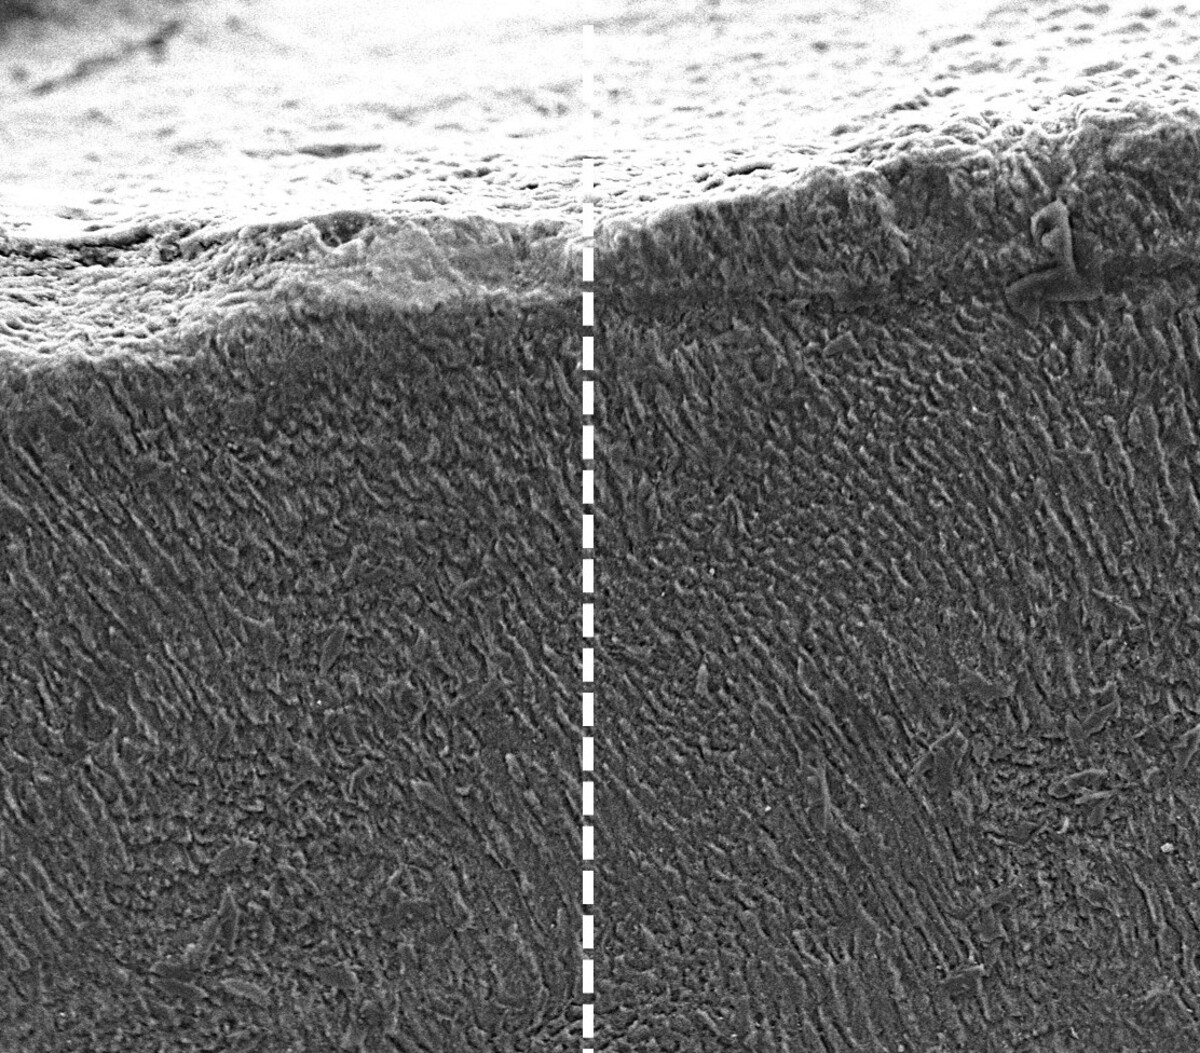

Πριν και μετά τη θεραπεία με κερατίνη από μαλλί προβάτου. Credit: Courtesy of King's College London

Πριν και μετά τη θεραπεία με κερατίνη από μαλλί προβάτου.

Αφότου οι ερευνητές εξήγαγαν την κερατίνη από ίνες μαλλιού προβάτου, την ανακάτεψαν με νερό και είδαν να σχηματίζει μια λεπτή μεμβράνη, την οποία εφάρμοσαν σε δείγμα δοντιού και διαπίστωσαν ότι σχημάτιζε μια διατεταγμένη, ισχυρή και κρυσταλλική επίστρωση, παρόμοια με το βιολογικό σμάλτο, όταν ερχόταν σε επαφή με μέταλλα στο σάλιο.

Κατά τη διάρκεια ενός μήνα, η επίστρωση προσέλκυσε ιόντα ασβεστίου και φωσφορικών, δημιουργώντας ένα σκληρό, προστατευτικό στρώμα πάνω από το δόντι.